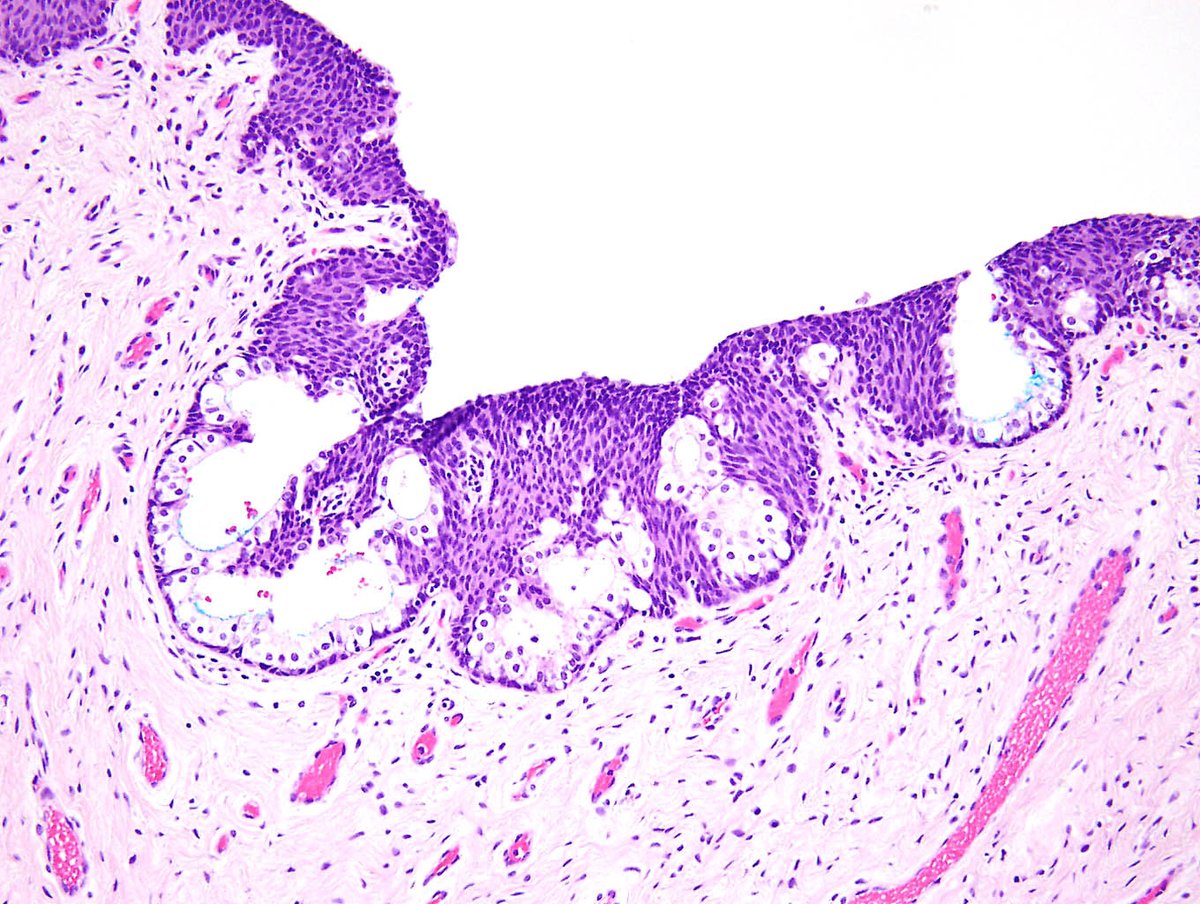

Yet another organ susceptible to prostatic metaplasia! Also interesting to speculate whether intraductal hair shafts with perductal inflammation could contribute to mastodynia in this population—

Prostatic metaplasia and pilar differentiation in gender-affirming mastectomy specimens go.nature.com/2Zif5FD

Why would vaginas resected in #genderaffirmingsurgery be carpeted by prostate? New paper showing #GYNPath in @AJSPjournal. Similar changes in hormone-treated #transgender patients and in #PediPath patients with endogenous androgen excess support a common cause!